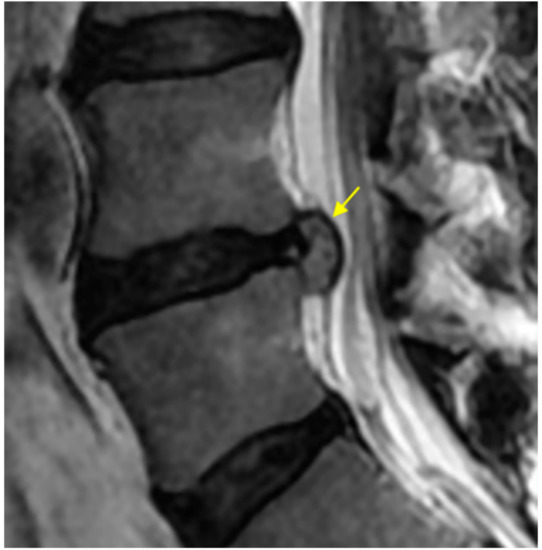

2.4.3. High-Intensity Change (HIC) of the Protruded Nucleus Pulposus (NP)